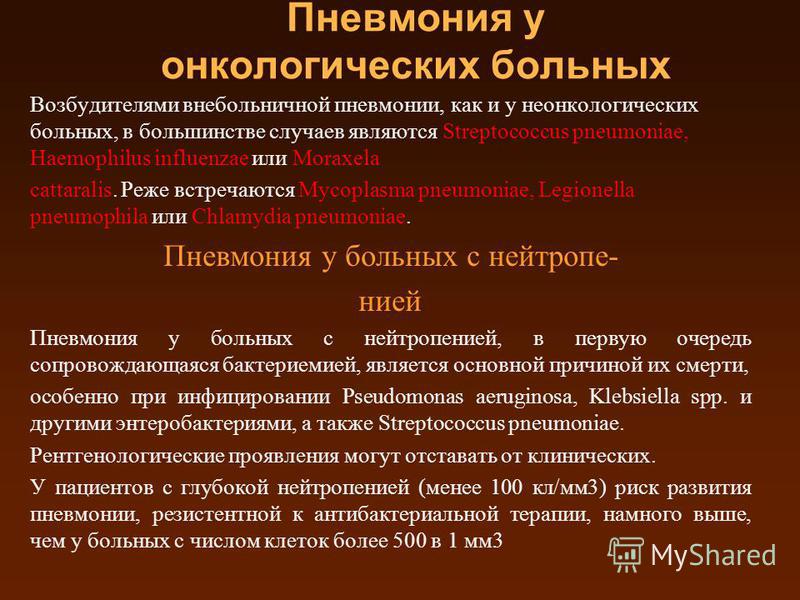

Острая внебольничная пневмония по МКБ-10: признаки и примеры